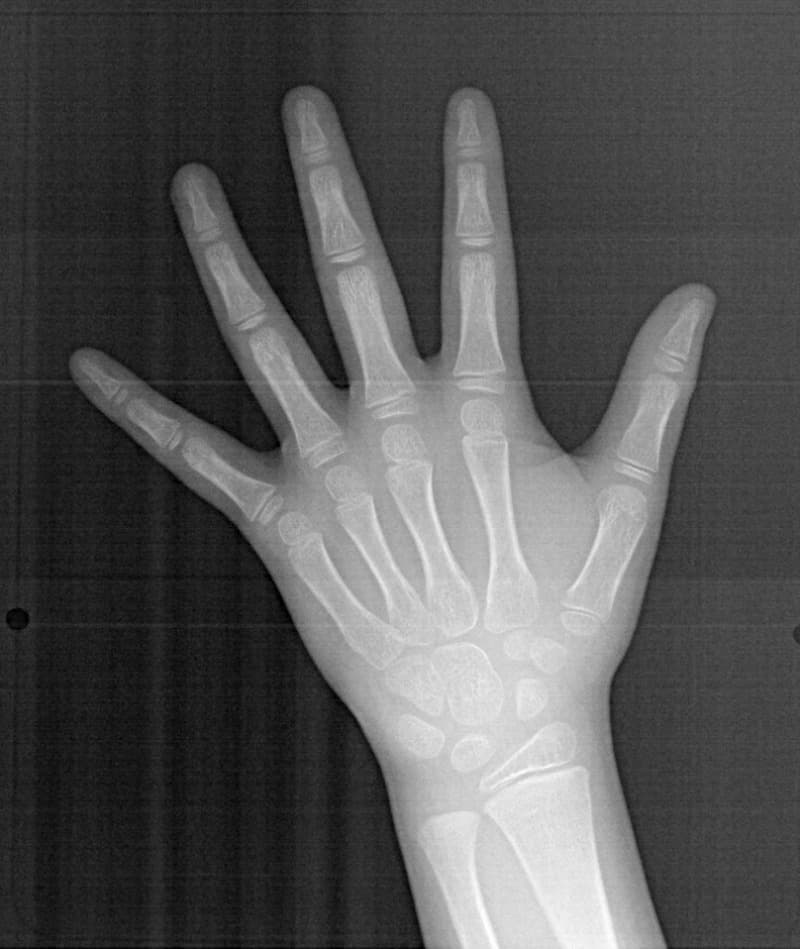

骨年齢は実年齢よりも低めなので、今後下顎の旺盛な成長が見込まれます。